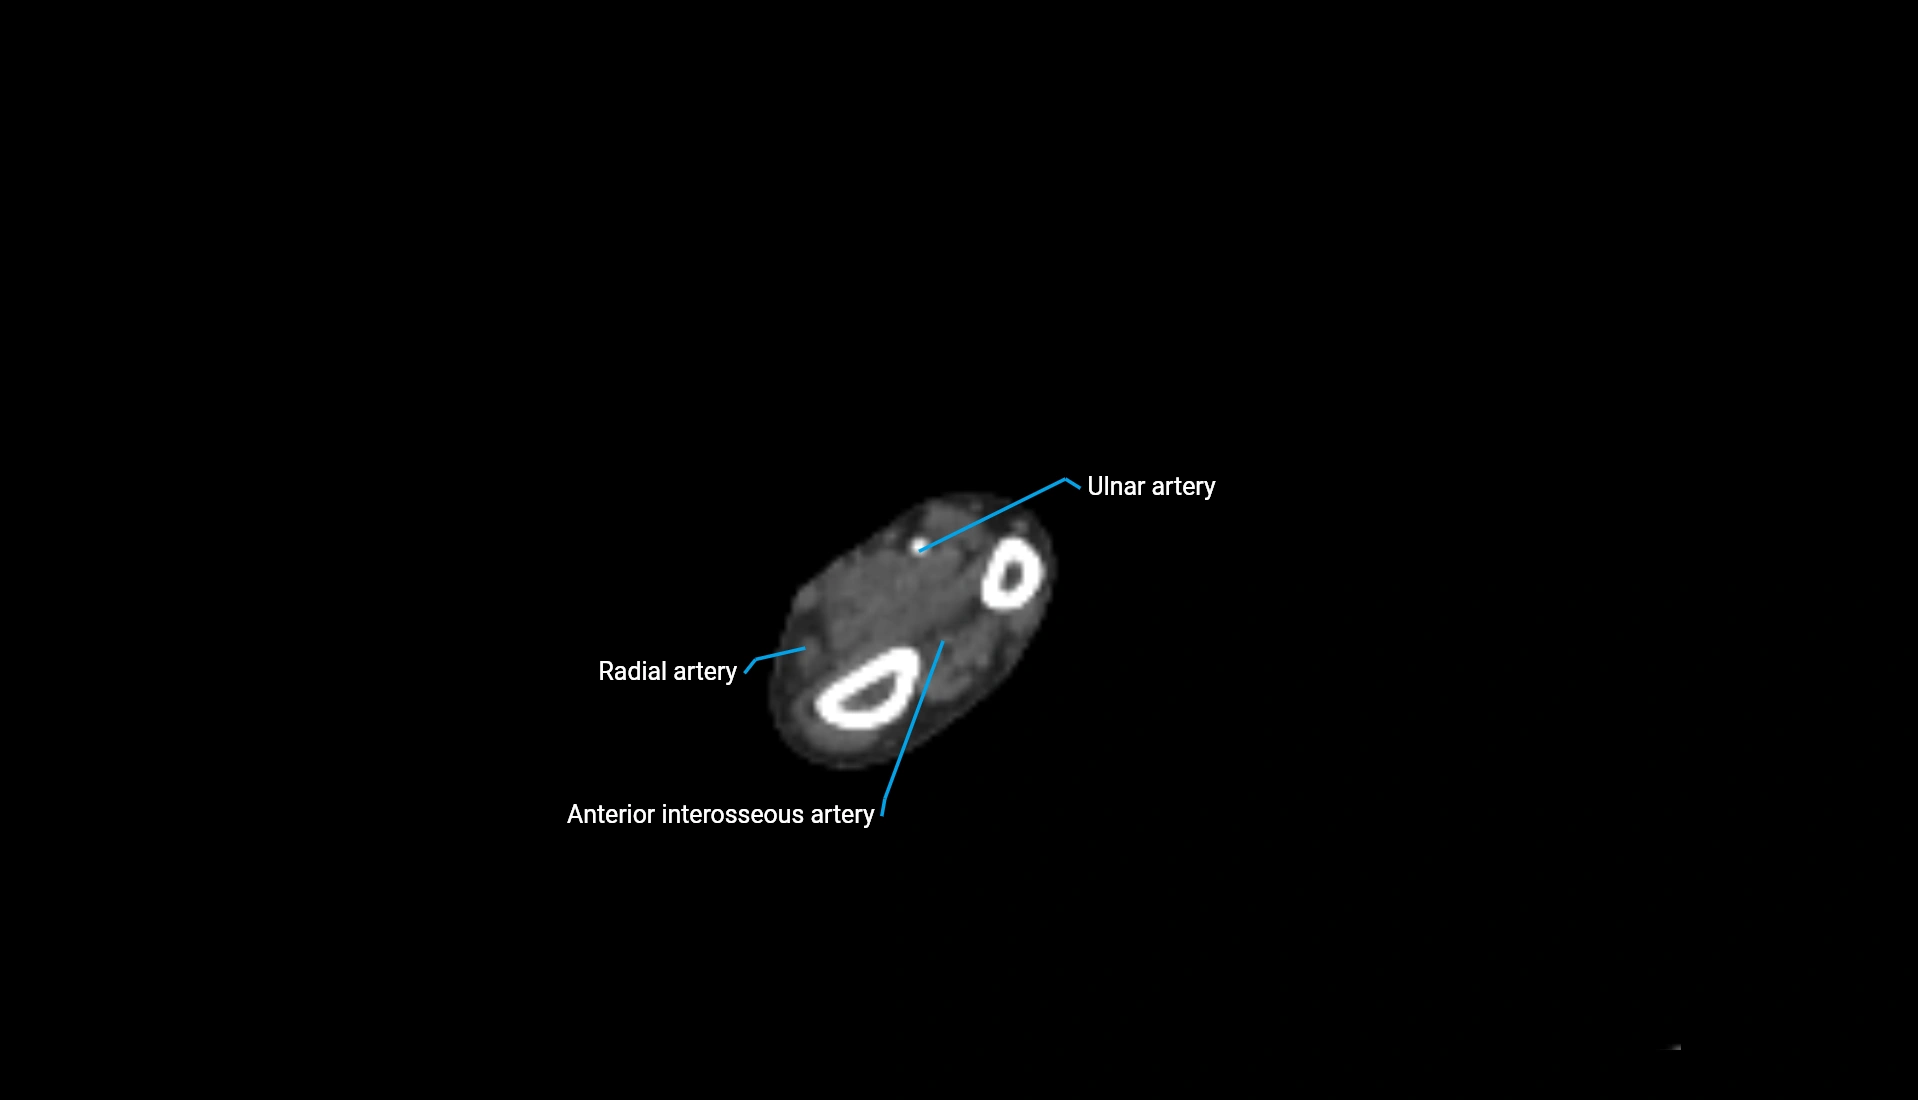

CT Appearance

Non-Contrast CT:

• Cortex: High-density, sharply defined

• Subchondral bone: Dense cancellous matrix

• Articular surface: Smooth concave contour articulating with the capitellum

• Excellent for evaluating bone integrity, alignment, and subtle fractures